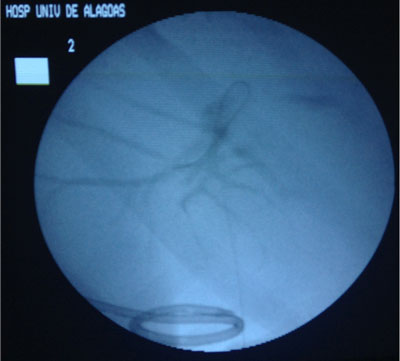

- Drenagem da Via Biliar e Dilatação da Estenose;

The main indications for a percutaneous treatment of a postoperative benign biliary stricture are:

(1) poor patient’s general condition that does not permit another surgical intervention,

(2) presence of altered anatomy that does not permit the endoscopic approach;

(3) septic status that requires a quick approach for decompression of the biliary tree.

Melhorar e manter a permeabilidade do ducto biliar, bem como prevenir a recorrência de estenose através de um procedimento minimamente invasivo.